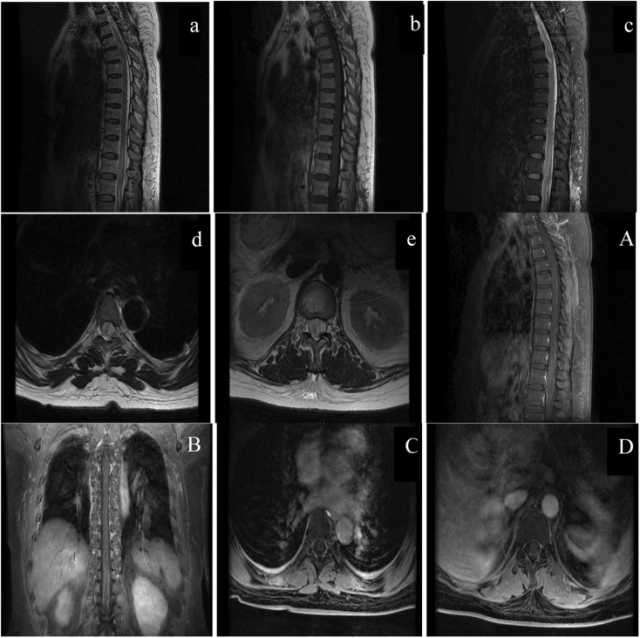

كانت نتائج مصل الدم والسائل النخاعي طبيعية أُجري التصوير بالرنين المغناطيسي (MRI) للدماغ والعمود الفقري باستخدام وحدة 1.5T (Signa HDxt وأظهرت الآفة زيادة في شدة الإشارة على الصور المرجحة T2 (T2WI)، وتقييد انتشار كبير على التصوير المرجح بالانتشار (DWI) وخريطة معامل الانتشار الواضح (ADC) ( الشكل 1ب ) و كشف فحص التصوير بالرنين المغناطيسي للعمود الفقري عن تورم منتشر وفرط شدة في الحبل الشوكي بأكمله على T2WI  ولم تظهر الآفة أي تعزيز للتباين بعد الحقن الوريدي للغادولينيوم (غير موضح). بناءً على نتائج التصوير بالرنين المغناطيسي هذه، تم الاشتباه في اعتلال الدماغ الأبيض السام.

الكلورفينابير مبيد حشري واسع الاستخدام، متوسط ​​الخطورة بينما أشارت تقارير سابقة إلى أن التسمم بالكلورفينابير قد يكون مميتًا للإنسان وقد أبلغنا عن أول حالة غير مميتة لاعتلال الدماغ الأبيض السام الناتج عن الكلورفينابير لدى امرأة تبلغ من العمر 44 عامًا، مع اختفاء شدة الإشارات غير الطبيعية في مسارات المادة البيضاء في جميع أنحاء الدماغ وجذع الدماغ والحبل الشوكي، وذلك باستخدام التصوير بالرنين المغناطيسي التسلسلي.